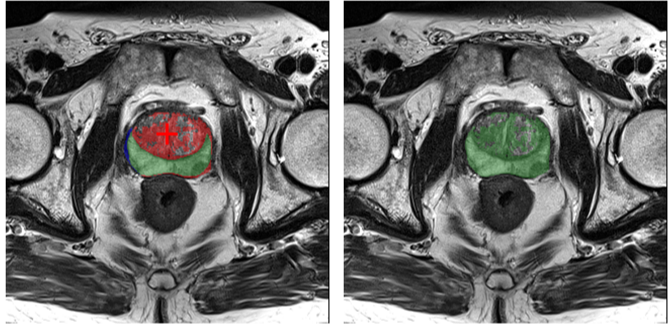

2. Privileged Information. While M2 writes from the agent’s perspective, it views a privileged “oracle” image. As shown in Fig. 7 (Left), this image explicitly visualizes segmentation errors: a Green Mask for True Positives, a Red Mask for False Positives (over-segmentation), and a Blue Mask for False Negatives (under-segmentation). It also indicates the “correct” next action (Positive/Negative point).

((a))

Refer to caption

((b))

Figure 7: Comparison of the “Oracle” view (for M2) and the “Agent” view (for M1) used in SFT reasoning generation.

Notably, this agent-visible mask (green) is the sum of the oracle’s True Positive (green) and False Positive (red) areas. M1 must learn to infer the expert’s corrective reasoning from this limited perspective.